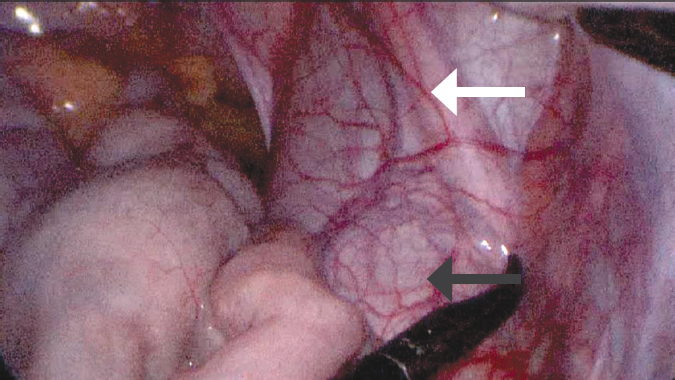

Fig. 2. Intraoperative view of a retroperitoneal formation protruding into the abdominal cavity (indicated by an arrow)

Рис. 2. Интраоперационный вид пролабирующего в брюшную полость забрюшинного образования (указано стрелкой)

Fig. 3. Type of detected retroperitoneal cystic formation (indicated by a black arrow), along the anterior wall of which the right ureter is visualized (indicated by an arrow with a contour)

Рис. 3. Вид обнаруженного забрюшинного кистозного образования (черная стрелка), по передней стенке которого визуализируется правый мочеточник (белая стрелка)

The patient was admitted to the operating room with a diagnosis of cystic pelvic lesion. Laparoscopic isolation of the mass with the pelvic part up to 10 × 7 × 5 cm showed that it ended blindly at the level of the round ligament of the uterus (Fig. 2–4). As the cystic mass was isolated more proximally, its tight attachment to the right ureter, stenosis, and extension towards the kidney were noted. The right kidney and its hilum were accessed, and the cystic lesion was found to be an atretic, highly dilated ureter of the lower segment of the duplex right kidney (Fig. 5). Its inferior segment was hypoplastic, measuring up to 12 × 10 × 10 mm, with virtually no parenchyma. Therefore, it was decided to perform an inferior heminephroureterectomy. The final view and schematic presentation of the extracted mass are shown in Figure 6 and Figure 7, respectively. The postoperative course was uneventful. The patient had no active urinary tract infections. Laboratory parameters of renal metabolism were normal, and early postoperative ultrasound showed no abnormalities in the remaining right upper kidney.